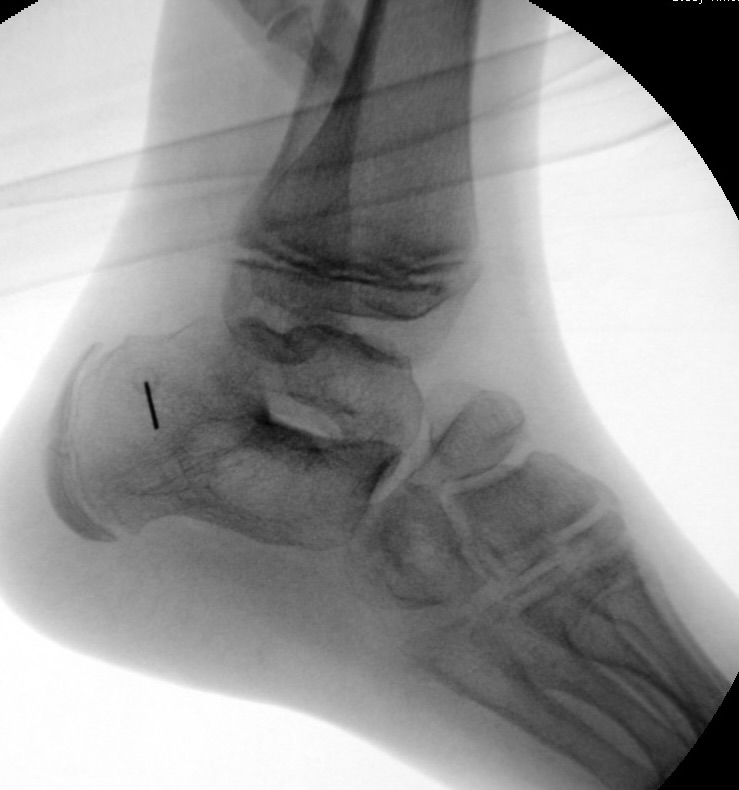

Calcaneus-Osteotomie

Die minimalinvasive Calcaneusverschiebeosteotomie bietet eindeutige Vorteile gegenüber dem offenen Verfahren, sodass wir bei Kindern und Jugendlichen nahezu keine offene Verschiebeosteotomie mehr durchführen. Am Calcaneus liegt die offene Wachstumsfuge dorsal. Bei der Durchführung müssen Schenkel der V-förmigen Osteotomie daher etwas steiler angelegt werden, in einem stumpfen Winkel (siehe Abb. 3 a-j). Für die Osteotomie liegen unsere Patienten auf dem Rücken und der BV wird für die exakte Seitaufnahme eingestellt. Der Fuß lagert auf einem hohen OP-Kissen und die Osteotomie kann bequem mit einem langen Kirschner-Draht und einem sterilen Stift angezeichnet werden (Abb. 15).

Abb. 3 a-j: Beispiel einer Calcaneusverschiebeosteotomie mit offenen Wachstumsfugen und der entsprechenden Osteosynthese mit Kirschner Drähten. Lokalisation der Osteotomie (a), Lage der Fräse (b-d), Drahtlage mehrere Ansichten (e-h), Heilung der Osteotomie 4 Wochen postoperativ und Entfernung der Drähte (i-j).

Abb.1 a-b: Beispiel einer noch offenen Wachstumsfuge im dorsalen Bereich des Calcaneus: (a) Alter 6 und (b) Alter 9 Jahre.